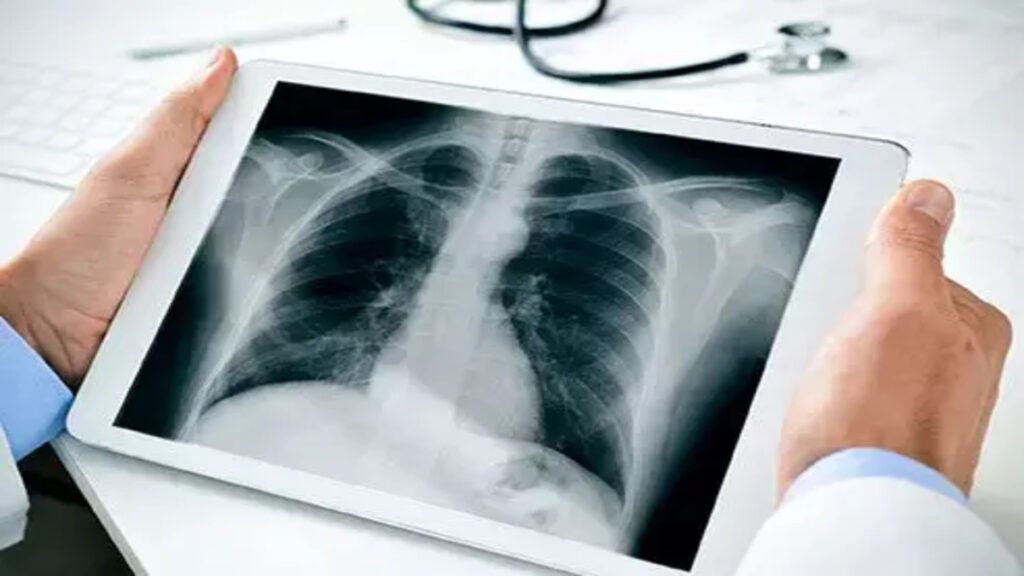

भिलाई। भिलाई के शहरी क्षेत्रवासियों के लिए बड़ी राहत भरी खबर है। वैशाली नगर विधानसभा क्षेत्र के निवासी अब मात्र 1 रुपये में एक्स-रे करवा सकेंगे। यह सुविधा 14 जनवरी से शुरू होगी।

इस योजना के तहत, भिलाई के निवासी अपने किसी भी एक्स-रे की जांच केवल 1 रुपये में करवा सकेंगे।